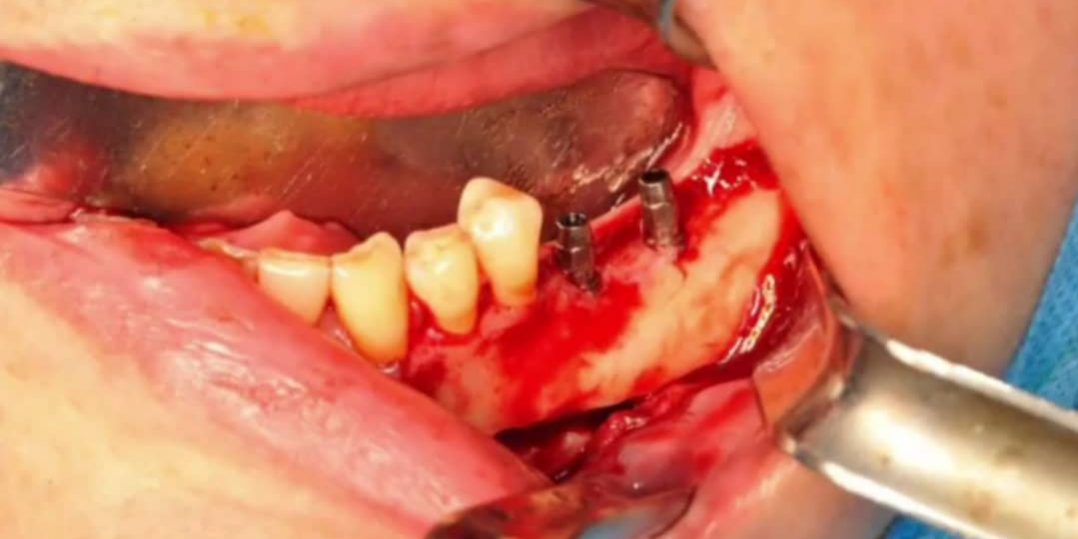

برای اولین بار در ایران جراحی جابجایی عصب فک پایین (Nerve transposition) با کمک گاید جراحی طراحی شده در مرکز دندانپزشکی دیجیتال و لابراتوار شرکت صبا تجارت مطمئن انجام شد.

جراحی (Nerve Transposition) یا همان جابجایی عصب روشی است رایج برای کمک در درمان ایمپلنت بیمارانی که به علت تحلیل استخوان ، ارتفاع استخوانی مناسب برای قرار دادن ایمپلنت در خلف فک پایین ندارند. در این جراحی عصب فک پایین از داخل استخوان خارج شده و سپس ایمپلنتهای بیمار با طول مناسب قرار داده میشود و دوباره عصب در محل خود برگرداندن میشود. در این بیمار با کمک طراحی دیجیتال، یک گاید جراحی که محل عصب را مشخص میکند برای بیمار ساخته شد و به کمک آن دقت و سرعت عمل در یک روش رایج به شدت افزایش یافت.

جراحی دیجیتال ابزاری است برای بهبود کیفیت و دقت جراحی و در عین حال خلق روشهای جدید .